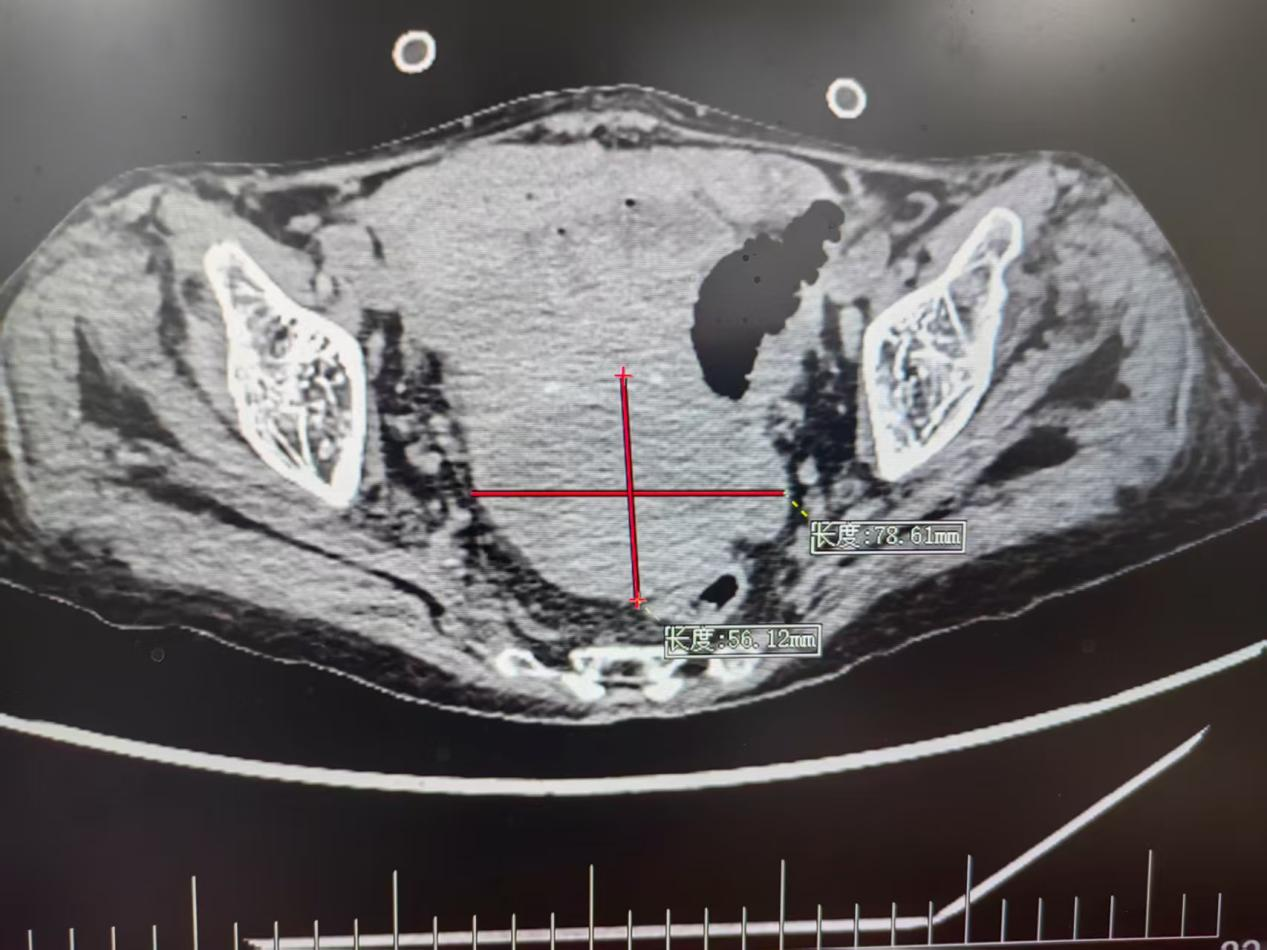

CT显示脓肿位置(红色“十字”部分)

张奶奶的求医路充满波折。不久前,她因“结肠癌破裂出血”紧急入院,胃肠外科团队紧急手术才将其从死亡线上拉回。可术后第23天,新的危机突袭:检查发现,张奶奶下腹部的子宫直肠凹(道格拉斯腔)里,长了一个大小约7.0×6.5×6.0cm的脓肿,这个深藏在盆腔深处的“感染炸弹”,若不及时处理,极可能引发全身性感染,再次威胁老人生命。

更棘手的是,这个脓肿的位置太特殊了:周围被重要器官与骨性结构包裹,用传统的经腹部穿刺路劲引流极易损伤肠道、血管等重要组织,常规方法治疗根本走不通。要是强行操作,稍有偏差就可能戳伤器官组织,引发大出血。看着老人痛苦的模样,家属急得团团转,医院医护团队也倍感压力,寻找“安全通道”刻不容缓。